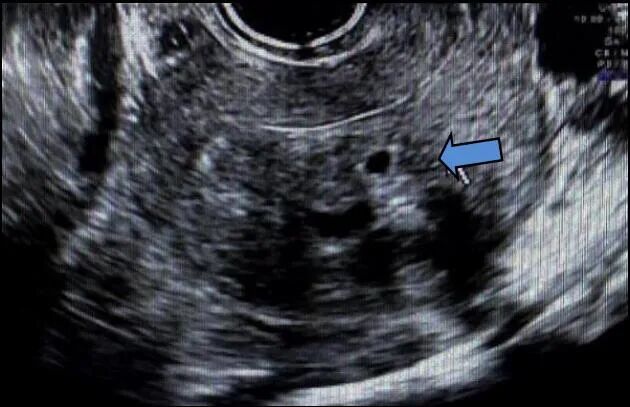

第二次手术后10个月,复查超声见子宫体大小约5.6 cm×6.6 cm×5.7 cm,肌层回声不均质,右后壁贴近宫腔并大部外突,非均质回声,范围约9.2 cm×7.6 cm×8.8 cm,内见暗区,大小约7.1 cm×5.5 cm×3.4 cm,内见细密点状回声;CDFI示非均质回声,周边可见条形血流信号,宫腔居中。肿瘤标志物CA125为236.5 U/ml。

术后4年余,自行触及下腹包块,超声提示子宫体大小9.1 cm×10.3 cm×7.0 cm,肌层回声不均,肌壁间可见多个低回声结节,较大位于左后壁,大小约10.1 cm×9.5 cm×8.3 cm,前壁较大结节,大小约4.9 cm×3.7 cm×3.9 cm;CDFI示周边及内部均可见条状血流信号,宫腔受压前移。

术后建议患者行基因检测,患者未遵医嘱。第二次手术后半年复查盆腔CT,提示子宫肌层强化不均匀,后壁见低强化结节,约2.5 cm×1.5 cm×1.5 cm。不除外肌瘤复发可能,予GnRHa治疗,现已注射4针,目前仍在随访中。